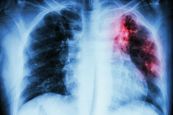

Bệnh lao là một bệnh lây nhiễm, trong đó phổ biến nhất là lao phổi. Thực tế, hiện nay nhiều người dùng từ “lao” và “lao phổi” để thay thế cho nhau. Vậy bệnh lao phổi có nguy hiểm không? Làm thế nào để điều trị lao phổi? Mời bạn tham khảo bài viết sau đây.